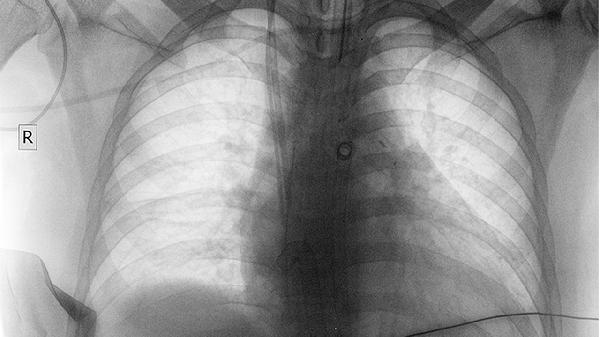

肺部瘤良性与恶性肿瘤的区别

肺部肿瘤的良性与恶性主要区别在于生长方式、转移能力及对机体的危害程度,良性肿瘤通常边界清晰且不转移,恶性肿瘤则具有侵袭性和转移性。

良性肺部肿瘤多呈膨胀性生长,与周围组织分界清楚,常有完整包膜,不会侵入邻近结构。例如肺错构瘤由正常组织异常排列形成,生长缓慢。恶性肿瘤呈浸润性生长,边界模糊,无包膜,可破坏周围肺组织,如肺腺癌常沿肺泡壁扩散。